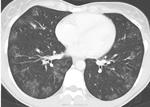

В ходе обследования обращало на себя внимание увеличение уровня лейкоцитов (20*109 /л) и эозинофилов  (40 %),  лимфопения (7%), СОЭ – 70 мм/ч при нормальном уровне гемоглобина,  повышение уровня IgЕ до 461 МЕ/мл. СРБ - резко положительный, гипергаммаглобулинемия. А анализах мочи патологических изменений не обнаружено.  Ан. мокроты: эритроциты 60-80 в п-зр,  эозинофилы 20-30 в п/зр, альвеолярные макрофаги – большое кол. МБТ, грибы не найдены. Спирография - выраженные нарушения вентиляционной способности легких смешанного типа. Бронхоскопия. 2- сторонний поверхностный эндобронхит (1 ст). Микрофлора не выделена.  В анализе кала без особенностей, гельминты и яйца глистов не обнаружены.  Анализы крови на p-ANCA, биопсия легочной не сделаны по объективным причинам.  Следует отметить, что только у 48–66 % пациентов в периферической крови определяются p-ANCA. Данные КТ при поступлении (см. рисунки). Наличие аллергии , аллергического ринита, бронхиальной астмы, гиперэозинофилии, лёгочных инфильтратов,  выпота в плевральной  полости, перикарде, лейкоцитоза, повышения СОЭ, повышения уровня СРБ, выраженной слабости, лихорадки позволили высказать предположение о синдроме Черджа-Стросса. Указанные признаки соответствовали второй фазе болезни.

Достаточно неспецифичная картина: билатеральное (больше справа) снижение пневматизации,  от зон "матового стекла" до консолидации с "воздушной бронхограммой", утолщение стенок бронхов, утолщение парасептального интерстиция, гидроторакс, немного жидкость в перикарде видна. Об узелковых изменениям по картинкам судить невозможно. Справа паракостально не то фиброз плевры, не то осумкованный гидроторакс - сказать трудно. Увеличения лимфоузлов средостения не разглядела, может, не в срезе или проблемно на преимущественно легочном окне увидеть.

Как раз исчезновение гидроторакса интересует меньше всего. В данном случае доказательством хронической консолидации, а не острой, будет сохранение её при адекватном лечении более месяца.

Для меня картина, более характерная (с учетом клиники, анализов) для хронической эозинофильной пневмонии.

Считается что для постановки диагноза синдрома Чардж- Стросса надо чтобы выполнялось 4 из 6 нижеперечисленных признаков:

1. Астма (у нас +) ;   в 50%  будет и при хронической эозинофильной пневмонии

2. Эозинофилия >  10 % (+); аналогично   и при ХЭП

3. Нейропатия (-) и другие системные поражения (кожа, ССС, ЖКТ) ;  при ХЭП нету.    Все таки в этом случае есть и именно он позволяет поставить правильный диагноз: это жидкость в плевральнйо полости и перикарде.

4. Изменения в ППН (+); однако данные измнения  могут быть и на фоне аллергического ринита при астме. (поэтому диф. критерий нечеткий)

5. Мигрирующий характер инфильтратов по КТ. Тут надо остановится поподробнее. Мигрирующий характера может быть как и при СЧС так и при ХЭП. Важно именно характер инфилтрации. В случае с СЧС инфильтрация в основном имеет дольковое распределение  - что это такое: посмотрите с ссылки что я выше привел картинки в конце статью - то есть выглядит как небольшие очаговоподобные инфильтраты. Также для СЧС характерна очаговость. В случае же ХЭП в начальные периоды преобладают именно консолидации, без четких контуров с вовлечением различных сегментов (хаотично). Мигрирующий характер консолидации также встречается часто.

То есть основным диф.диагностическим критерием по КТ между СЧС и ХЭП будет именно ХАРАКТЕР ИНФИЛЬТРАЦИИ. В нашем случае - характер больше в пользу ХЭП (она более массивная , явных признаков очаговости процесса не видно)

Так что я бы не торопился ставить явно без вопросов диагноз СЧС. Согласен с Любовь С., что  радиологическая картина (учитывая наличие массивных консолидаций, уже с признаками фиброзироваия) похожа на ХЭП. (но учитывая наличия жидкости в плевральнйо полости и в перикарде - все таки СЧС)

Сорри , написал пост - потом еще раз все пересмотрел - больше в пользу СЧС. Все решил гидроторакс и гидроперикард :)) А вот критерий характера инфильтрации к сожилению не такой четкий. Но при СЧС все таки очаговоподобность больше. Если бы не было системности поражения - то ставил бы все таки ХЭП.